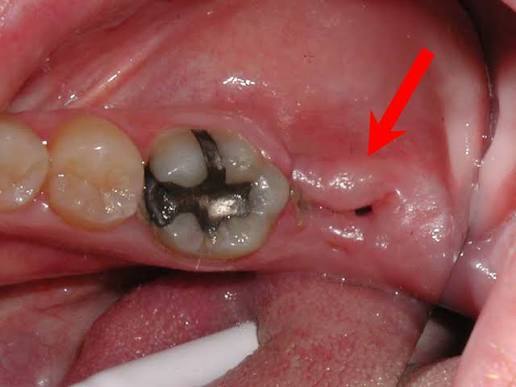

Klinička slika alveolitisa

Klinička slika alveolitisa sa svim simptomima najčešće se ne opaža u prva dva dana nakon ekstrakcije zuba i javlja se dva do tri dana nakon vađenja. Najupečatljivija promjena je, pored intezivnog bola, odsustvo normalnog koaguluma tj. krvnog ugruška u alveoli u kojoj je bio zub. Alveola je ispunjena ili slabim, sivim ugruškom neprijatnog mirisa ili je potpuno prazna, te je eksponirana kost. Upravo ova činjenica objašnjava zašto je ovo veoma bolna komplikacija. Kako se u zidovima alveole nalaze nervni završeci, ukoliko ne budu pokriveni krvnim ugruškom, biće veoma bolni i na najmanji podražaj. Ono što je najbitnije da pacijenti znaju za alveolitis jeste da on NE predstavlja infekciju.

Neophodno je da stomatolog, poslije vađenja zuba, sačeka da se alveola ispuni krvlju, a ne pljuvačkom. Ako je aveola suva neophodno je isprovocirati krvarenje. Kao što je već rečeno, alveolitis predstavlja poremećaj organizma da stvori u datom trenutku normalan koagulum. Alveola je ispunjena raspadnutim i rastresitim koagulumom, koji je prljavo sive boje, neprijatnog mirisa i koji se vrlo lako kida pincetom (alveolitis exudativa), mada alveola može da bude i potpuno prazna (alveolitis sicca). Sve intervencije koje se rade u smislu liječenja alveolitisa, a to su uklanjanje “lošeg” koaguluma, ispiranje alveole, provociranje krvarenja (zarad stvaranja novog koaguluma) kao i postavljanje medikamenata, rade se uz upotrebu lokalne anestezije.

Prije postavljanja dijagnoze alveolitisa ponekad je potrebno napraviti rendgen snimak alveole da bi se isključilo prisustvo zaostalog korijena, stranog tijela ili koštanog sekvestra. Iako alveolitis sam po sebi ne izaziva neke ozbiljnije komplikacije, bol, zbog svog intenziteta, uveliko ometa svakodnevne aktivnosti pacijenta, pa ga je potrebno liječiti.